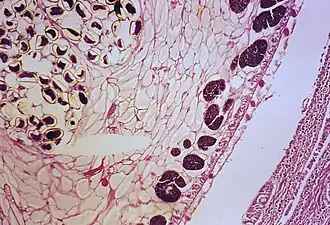

![]() Часть взрослой особи лёгочной двуустки в просвете бронха, крупные фиолетовые пятна — созревающие яйца. Окрашенный гистологический препарат | |